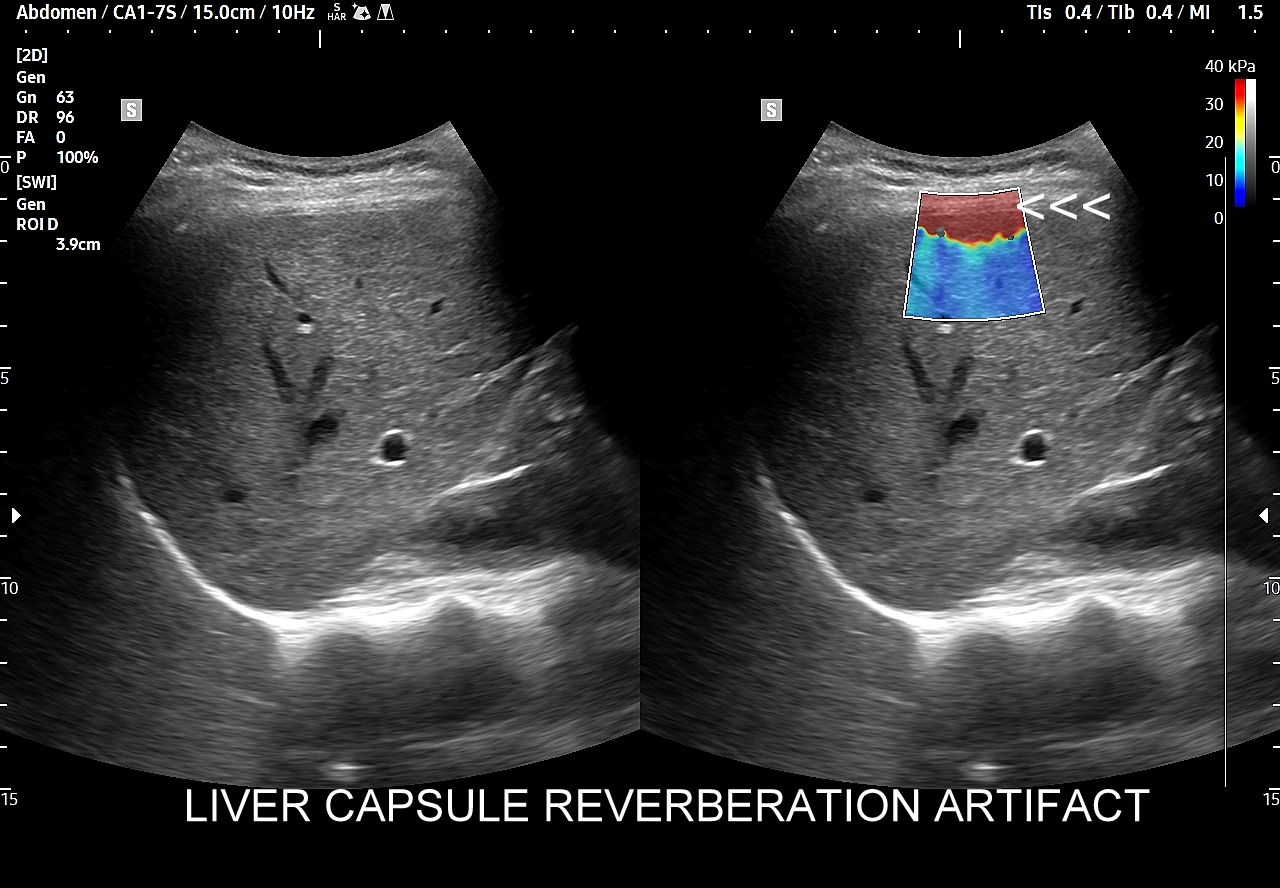

1/ Artefakt rewerberacji torebki wątroby (ang. liver capsule reverberation artifact) i podobne. W pobliżu torebki wątroby, jak i innych szerokich powierzchni, powstają zwykle rewerberacje akustyczne, które mogą fałszywie zawyżać wartości sztywności tkanki wątrobowej. W obrazowaniu 2D-SWE artefakt ten uwidacznia się jako występujący na obwodzie i tuż pod torebką wątroby, zwykle jednolity i kodowany na czerwono, równoległy do zarysu narządu obszar fałszywie zawyżonej sztywności. W celu uniknięcia tego artefaktu pomiary należy wykonywać na odpowiedniej głębokości narządu z dala od jej zewnętrznego zarysu i pod kontrolą mapy koloru.